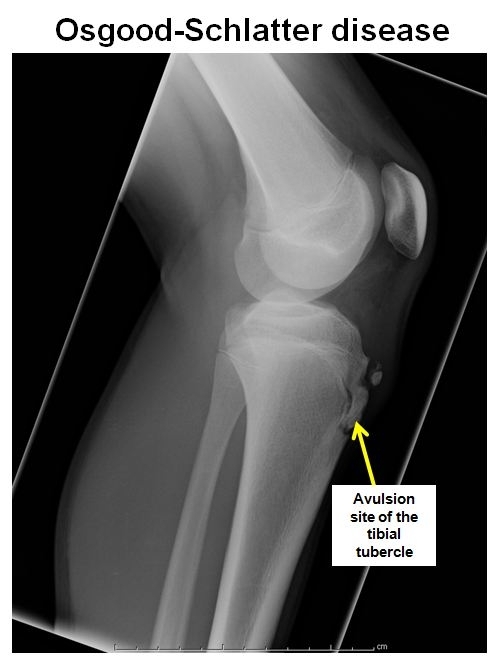

Osgood Schlatter

.,

X-ray of the knee typically shows avulsion of the apophysis of the tibial tubercle.